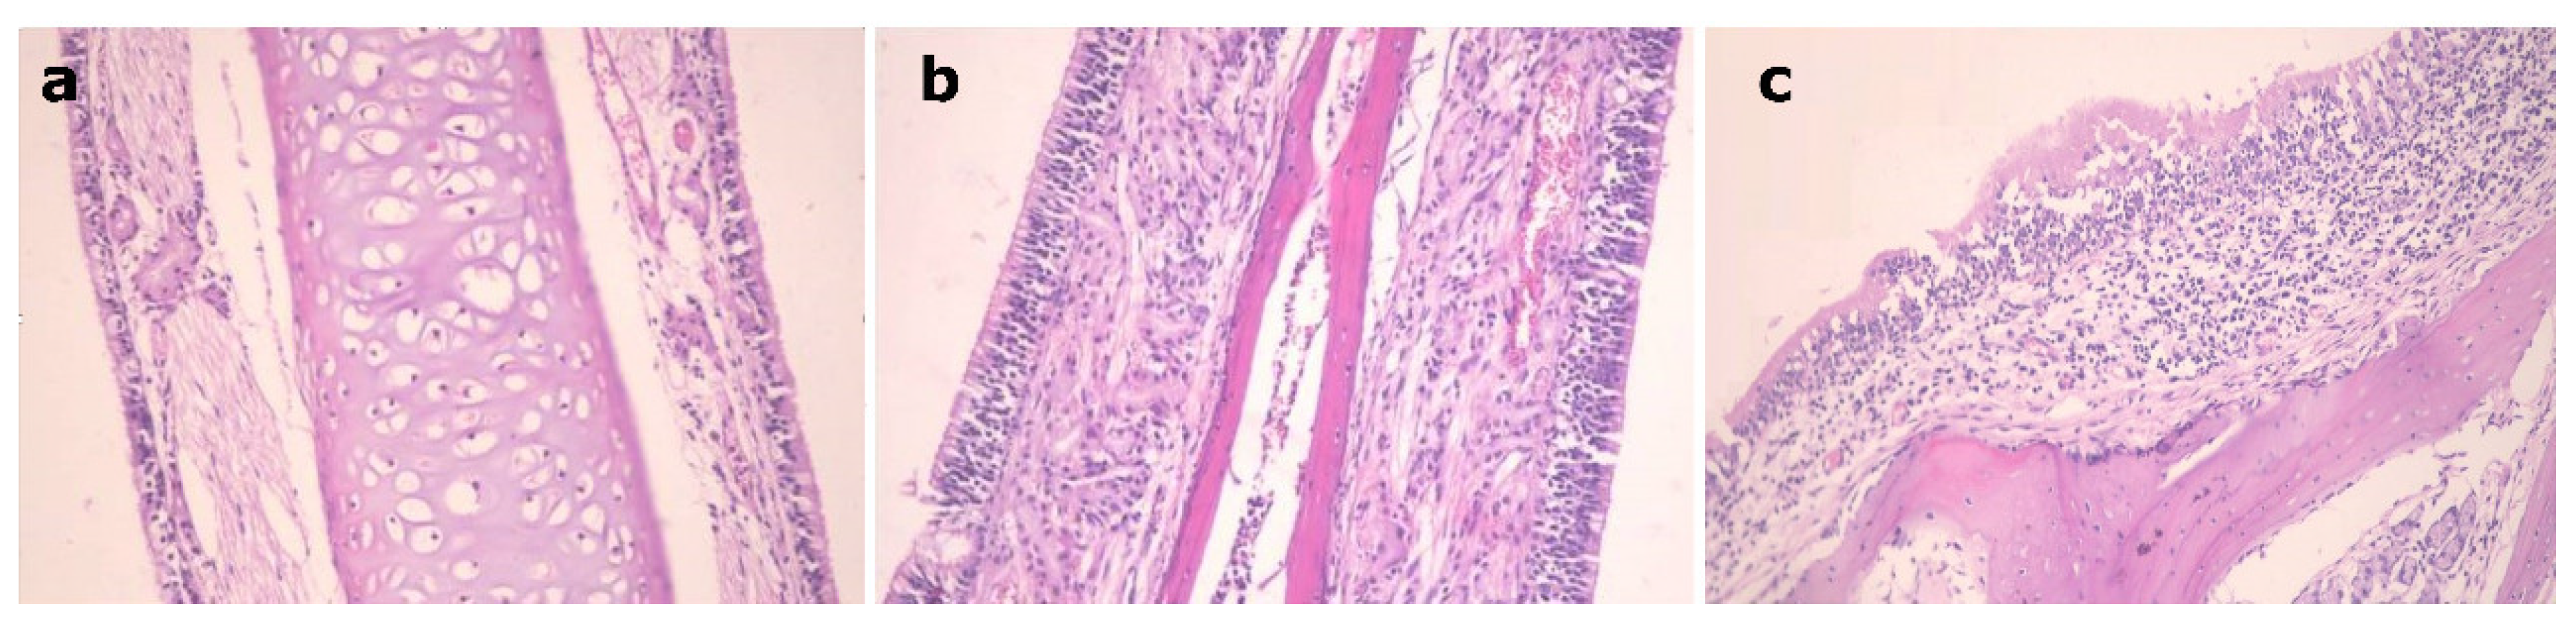

3.7. Histopathological Study